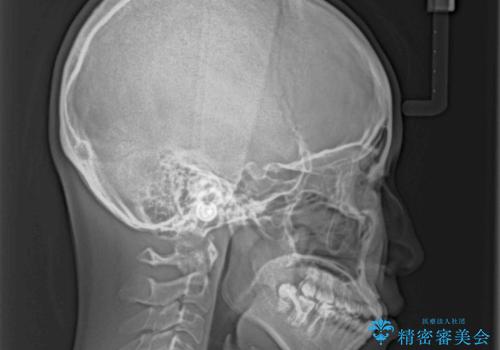

単純に上下左右の第一小臼歯4本を抜歯して口元の突出感を改善することも考えられましたが、上顎骨よりも下顎骨の幅が広いため、より良い咬み合わせを達成することを目的として、急速拡大装置を用いて上顎骨を拡大することとしました。

歯列矯正では基本的に骨格を改善することはできませんが、急速拡大装置(MARPE)を使用することで上顎骨を側方に拡大させることができ、咬合状態を大きく改善することができます。